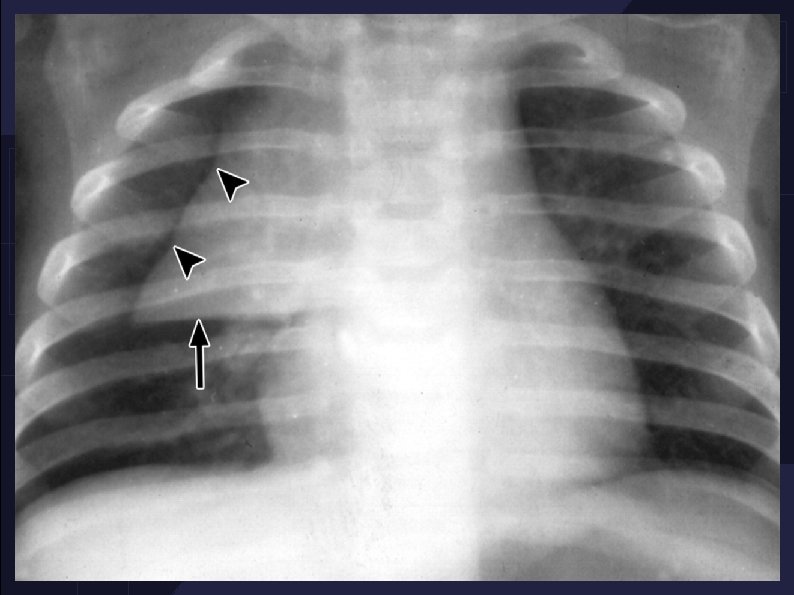

Thymic rebound hyperplasia in an 11 -year-old girl with Hodgkin lymphoma.